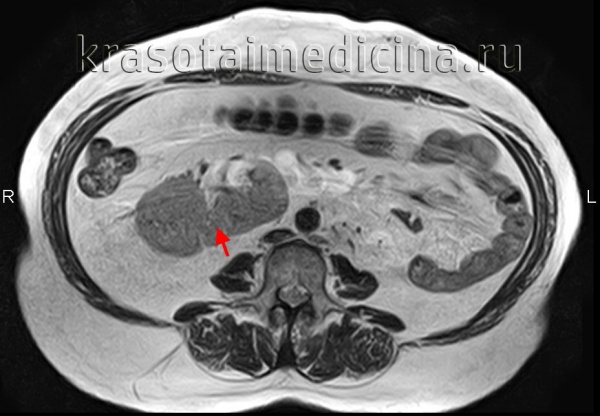

3. МРТ при перекрестной эктопии почки у плода:

• Показана при подозрении на аномалию сращения почек

4. Рекомендации по лучевой диагностике:

• Эктопическую почку подтверждают обнаружением гипоэхогенных пирамид мозгового вещества

• Почечную артерию эктопической почки обнаруживают с помощью допплерографии

3. МРТ при эктопии почки плода:

• Прибегают в случае затруднительной диагностики:

о Позволяет отличить эктопическую почку от кишечника

о Помогает отличить почечную паренхиму от солидного или кистозного образования малого таза